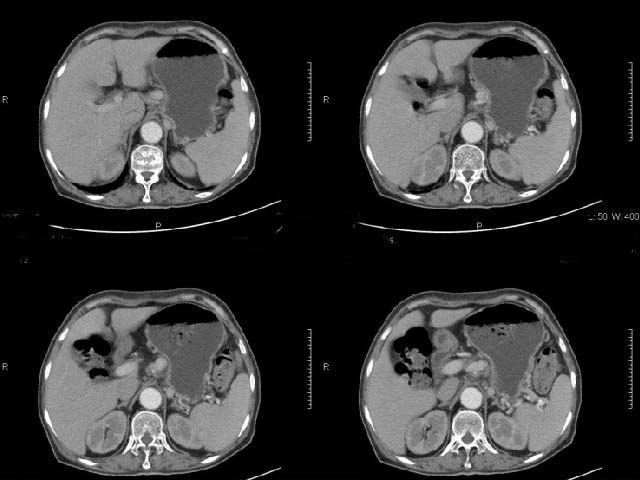

女,69岁,浑身乏力,腹泻半年余,无腹疼,排泄物中含有脂肪球,抗炎治疗一周仍不缓解,来我院检查发现明显低钾血症,给予补钾(氯化钾)一周后,血钾恢复正常,经化验检查,尿钾持续明显高于正常,临床考虑患者不仅消化道失钾,还伴有泌尿系统失钾,故进行ct增强检查看肾上腺是否有病变。ct表现为胰腺肥大,而且体尾部强化较弱,明显呈稍低密度,胰尾见有更低密度,而且胰腺与周围组织的脂肪间隙不清,大血管周围似乎有包绕现象,患者是否有过胰腺炎病史,家属说不清楚;而双侧肾上腺大小形态,本人认为未见异常,本人倾向于考虑:慢性胰腺炎伴假性囊肿,不排除胰腺占位可能;但是不知怎么解释持续尿钾现象。请大家发表高见!

平扫